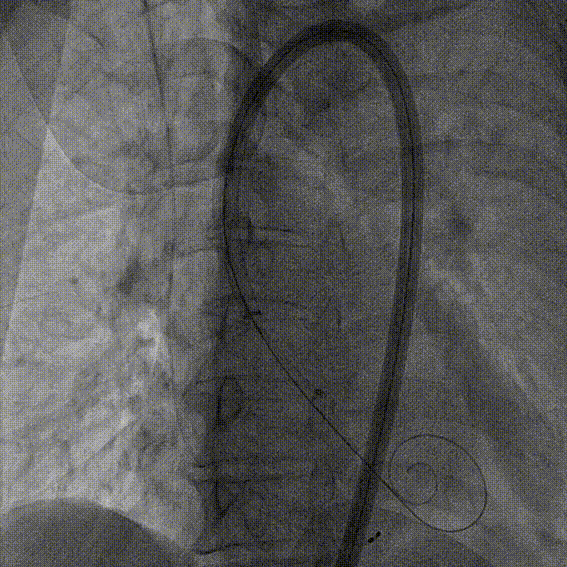

右窦中心造影

大鞘到STJ

瓣膜调弯后解离

瓣膜右窦中心调整

定位键窦不对齐

灵活旋转操作

确认窦对齐

入窦

无窦超选验证

左窦超选验证

一键释放